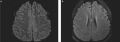

Figure 2: (a) Magnetic resonance imaging using fluid-attenuated inversion recovery shows multiple small bright lesions with areas of cortical involvement. (b) Magnetic resonance imaging using diffusion-weighted imaging demonstrates multiple bright lesions on both sides of the brain. Open access under terms of the Creative Commons License 4.0: https://creativecommons.org/licenses/by-nc-nd/4.0/. Original figures available at: https://doi.org/10.7861/clinmed.2022-0166